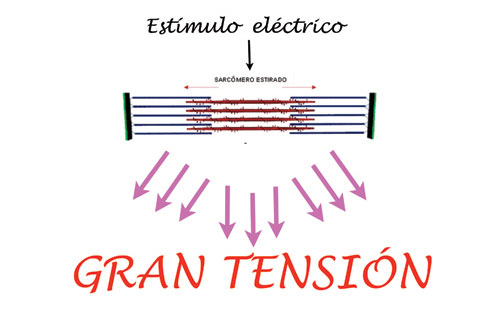

Por el contrario , si el músculo es elongado en su longitud, es decir con sus sarcómeros estirados, la tensión de contracción es enorme.

DIBUJO II